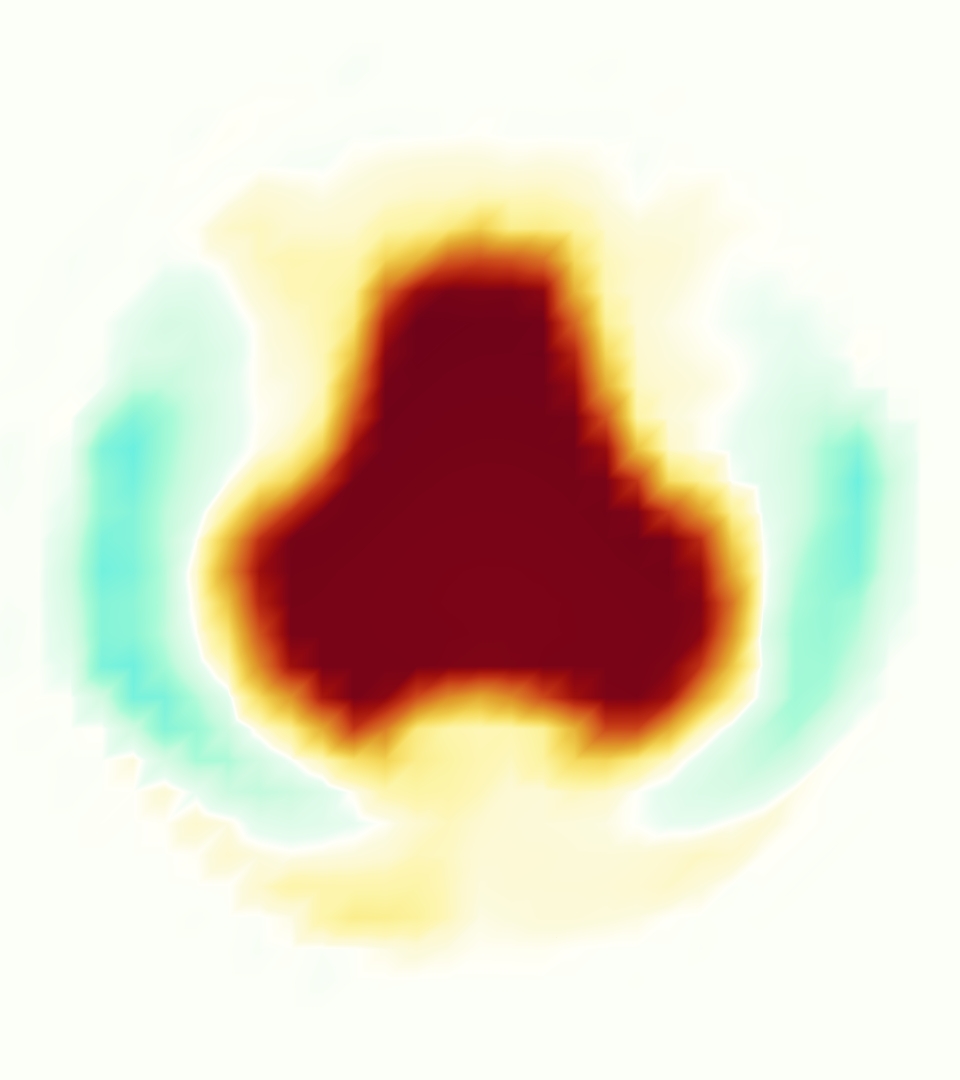

Slice views of the (axial) component of fluid velocity in the axial plane, orthogonal to the flow direction, show that the simulation replicated the development of the jet over the cardiac cycle. At each phase, the simulation matched the forward speed of the core of the jet and the locations of reverse flow back towards the valve annulus. While there are some differences in the shape of the jet at certain phases and locations, the simulation clearly produced the general dynamics of the cardiac cycle that are seen in the experiment.

At = 0, the axial slice directly at the valve annulus shown in columns 1 and 2 in Figure 6, there was excellent agreement between the simulation and experiment over the cardiac cycle in the speed and shape of the jet through the valve. In both cases, the axial velocity increased as the flow accelerated during systole and the valve leaflets opened, then decreased during diastole with slight negative velocity before the valve leaflets were fully closed. The forward flow through the valve annulus did not form a full circle, but rather developed a triangular shape with a point of the triangle forming along the interior curve of the vessel, at the bottom of the axial slices. At = 0, the points of this triangular jet shape aligned with the commissures of the valve. This shape persisted during peak systole and was well-matched by the simulation.

The axial slice = 0.625 cm, shown in columns 3 and 4 in Figure 6, cut through the support scaffolding of the valve and the leaflets when they are open. In the experimental data, the shape of the jet changed as it moved downstream. A triangular shape occurred, but the points were then aligned with the middle of each open leaflet as opposed to the commissures. Those points were also more rounded than they were at = 0. The peak velocity of the jet was faster at = 0.625 cm than at = 0, as the flow accelerated through the open valve leaflets. The simulation produced these features at = 0.625 cm. The triangular shape of the jet shifted similarly, and its speed increased compared to the upstream slice. As the flow decelerated into diastole, the jet shape remained roughly triangular but diminished in intensity before disappearing after valve closure.

The jet continued to develop at = 1.25 cm, an axial slice immediately downstream of the valve scaffolding and open leaflets, shown in columns 5 and 6 in Figure 6. In the experimental data, the points of the triangular jet shape extended further towards the vessel wall. In addition, regions of reversed flow developed in the locations downstream of the commissures, resulting in curved sides to the shape of the jet. Each tip of the jet was unique, due to variations in the individual leaflets in the physical bioprosthetic valve. These variations are apparent in the velocity fields, possibly because the jet edges are similar enough cycle to cycle that irregularities are still being captured even with phase averaging. Further discussion of these features can be found in Schiavone et al. [39], which showed that the jet tip shapes occurred in different pulmonary anatomies, demonstrating that they were likely due to inherent properties of each leaflet. The leaflets in the mathematical model of the valve are identical, so these nuances in leaflet variation could not be replicated. The simulation did capture some of the extension of the tips of the jet, as they were closer to vessel wall at slice = 1.25 cm than = 0.625 cm. The curves in the triangular sides of the jet were also present in the simulation, though they were less pronounced than the experimental data. At both = 0.625 cm and = 1.25 cm, the jet shape in the simulation was smoother than the jet in experiment. It is possible that the free edges of the leaflets in the mathematical model are not fully replicating the behavior of the physical leaflets of the bioprosthetic valve, in particular the amplitude or frequency of leaflet flutter, leading to the variations seen in the jet shape at = 1.25 cm downstream of the leaflet edges. The simulation, however, does capture the key features of the triangular shape and speed of the jet. Overall, qualitative comparisons demonstrated that the simulation reproduced key features of the flow during systole and diastole.

The phase-averaged, resampled velocity fields during peak systole and flow rates at each resolution are shown in Figure 10. Despite the limitations discussed above, we observe similar qualitative trends in the flow field at all resolutions. At all resolutions, a jet formed and angled up downstream of the valve orifice, as shown in the sagittal view. The jets showed a triangle-like cross section at with points aligned with the commissures. At cm, the jet appears like a rounded triangle in the opposing orientation, with its points aligned with the center of the leaflets. At cm, the jet is narrower downstream of the commissures, and wider downstream of the leaflets, again with a triangle-like cross section. The area of the jet increased with resolution, as expected given the IB method thickening of the valve structure. The narrowed jets at the two more coarse resolutions show locally elevated velocities relative to the two more fine resolutions. Figure 11 shows the instantaneous velocity fields at each resolution in the same axial and sagittal views. At 0.9 mm, the sagittal view shows a qualitatively different jet than at finer resolutions, with regions of lower velocity farther from the vessel wall, indicating insufficient resolution. At 0.9 and 0.68 mm, the jet is visibly narrowed compared to higher resolutions. While some features are similar at these two coarse resolutions, we conclude that the narrower jets indicate these simulations are under-resolved. Flows in the three finest resolutions, 0.45, 0.34 and 0.28 mm. appeared qualitatively similar, with slightly more fine structure detail in both the axial and sagittal views present at the edges of the jet. The jets in the axial views all showed a similar triangle-like cross section, slightly narrower downstream of the commissures, as in the phase-averaged fields. In both the phase-averaged and instantaneous fields, the three finest resolutions appear sufficiently similar that the conclusions of this study would be identical with any of these resolutions.